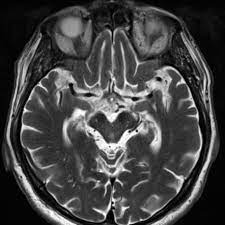

Structural Mri In Idiopathic Parkinson Disease And Parkinsonism Radiology Key